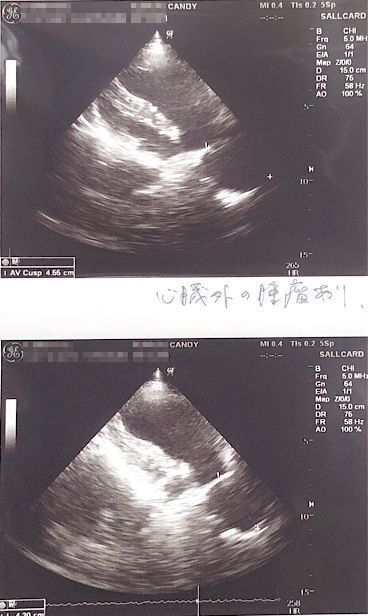

エコーを撮ったところ、体の中心に腫瘍の影があるのが見えると言われました。

↑バリウム飲んで検査してもらった所、矢印の部分に腫瘍があり(白い部分は食道)、それが食道を押し上げているため、飲んだ水を吐いたりするとの事でした。(この時点で5センチほどの大きさの腫瘍)

↑腫瘍の場所が体の奥のにある為、CT検査できる大学病院で検査してから手術するかどうか決めたほうがいいと言われました。